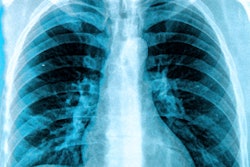

Black lung became such a scourge that in 1969 the U.S. government established the Federal Coal Mine Health and Safety Act, which gave NIOSH the authority to run a screening program to detect early signs of black lung in miners. The program offered chest x-ray screenings to coal workers, with images read by NIOSH-certified physicians, informally called B readers. Miners found to have black lung became eligible to receive disability benefits paid for by their employer.

To analyze the trend in more detail, the NIOSH researchers looked at the prevalence of coal workers' pneumoconiosis on radiographs acquired of workers in underground mines from 1970 to 2017 that were collected as part of the screening program. Coal workers' pneumoconiosis was defined as the presence of small opacities with profusion category of 1/0 or greater on the International Labour Office Classification of Radiographs of Pneumoconioses scale. Progressive massive fibrosis was defined as any large opacity greater than 1 cm.